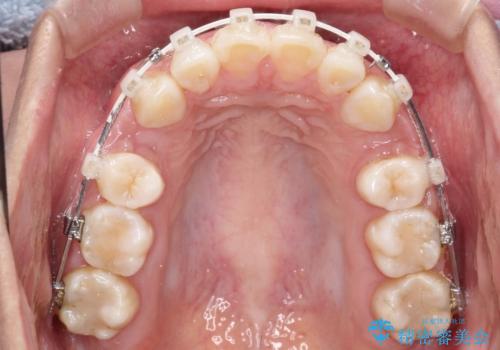

- 矯正装置

- 審美装置

- 出っ歯を主訴に来院されました。

下の歯並びに対して、上の歯が全体的に前方に位置している状態でした。

上の歯の前から4番目の歯を2本抜歯して、そのスペースに前歯を移動させて、前歯を引っ込める計画としました。